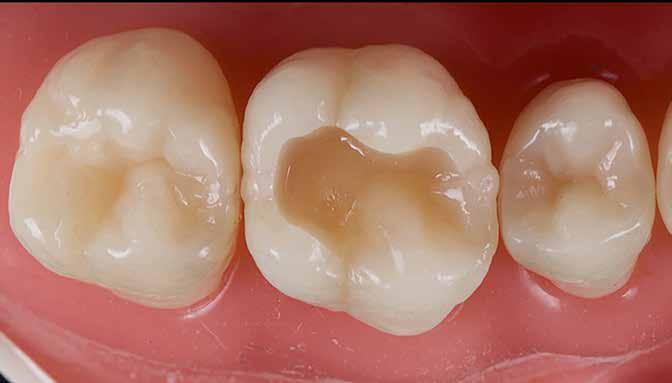

A restauráció polírozását korongok és szilikonpolírozók kombinációjával végezte, majd az okklúzió ellenőrzését követően a pácienst a rendelőből otthonába bocsátották. Megjegyzendő, hogy a finírozást követően az eredeti okkluzális anatómia csak minimális mértékben módosult (17. ábra).

2. eset

Egy 26 éves páciens a jobb felső első molárisának ideiglenes, endodonciai kezelést követő, I. osztályú restaurációjával jelentkezett. Mivel a fogban jelentős mennyiségű dentin és zománc volt jelen, valamint a marginális peremek épek voltak, a páciens tájékoztatása és beleegyezése után a kezelési terv a direkt kompozit restauráció volt (18. ábra). A fog preparálása az 1. esetben leírtak szerint történt (19. ábra).

Végül a szerző az üreget a „Modified Super-Closed Sandwich Approach” [20] technikával állította helyre (amely a klasszikus rezin-módosított üvegionomer zárt-szendvics technika módosított változata), és az okkluzális iránytű módszerét alkalmazta a rágófelszín lezárására (20. ábra).